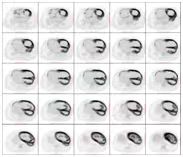

医师决定行二尖瓣机械瓣置换术(保留瓣下结构),三尖瓣成形术,房间隔缺损人造补片修补术,动脉导管未闭切段缝合术。术前为排外手术禁忌证,2022.11行PET/CT示:巨大心脏显影,房室各壁心肌代谢明显增高。

(图1)先天性心脏病患者(女,41岁)18F-FDG PET/CT显像图。1A.全身最大密度投影图示心脏明显扩大,房室各壁糖代谢明显增高;2B.心脏断层显像示各室壁糖代谢明显增高,SUVmax为11.5;1C.横断面、冠状面、矢状面三个不同层面示心腔明显增大,各室壁糖代谢明显增高。图2同一患者胸片。2A.2022年10月(手术前)胸片:心胸比为0.88;2B.2022年12月(手术后)胸片:心胸比例为0.76。